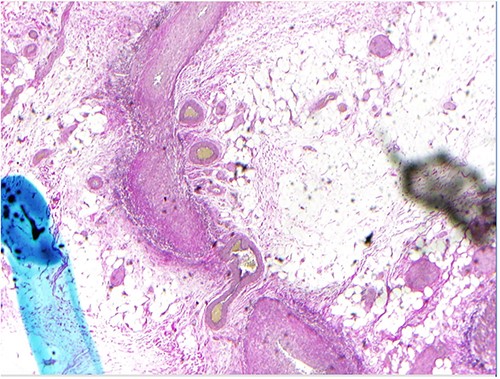

Colonoscopy showed an unremarkable rectal mucosa; however, starting in the sigmoid colon, there was diffuse circumferential ulceration and evidence of a necrotic mucosal lining (Fig. 1). The area was ulcerated and firm, extending from the sigmoid colon, through the descending colon, to the splenic flexure. Once at the splenic flexure, the remainder of the colon and terminal ileum were unremarkable for significant inflammation. These findings raised concern for ischemic-type injury rather than inflammatory bowel disease. A subsequent CTA was primarily notable for left colonic thickening, hypoenhancement, and multiple aneurysms and irregularities of the inferior mesenteric artery in a distribution concerning for vasculitis (Fig. 2). Rheumatological recommendations included a laboratory workup with: antinuclear antibody, antineutrophilic-cytoplasmic antibody, cytomegalovirus, histoplasma, treponemal, hepatitis panel, which all returned negative.

Colonoscopy: diffuse circumferential ulceration and a necrotic lining.